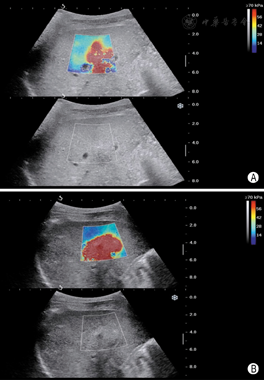

孕妇26岁,孕1产0,孕12+5周,以外院诊断腹部囊实性包块来我院进一步检查。患者及其配偶体健,无其他病史及不良习惯,家族中无类似患者,患者否认直系三代有遗传病史及遗传倾向疾病。二维超声检查:胎儿颅骨光环完整,双侧脉络丛发育正常;胸腔内未见明显异常,心脏可测得四腔心、左右室流出道;胎儿腹部可测及大小约2.28 cm×1.9 cm的囊实性包块,向外突出,其内可见胃泡,另见一囊性无回声,大小约2.0 cm×1.8 cm,两侧可见脐动脉;胎儿下腹部囊性包块左侧测及两条平行骨性回声,可见一侧脚板;双上肢可见;胎儿肾及肾动脉显示不清;胎儿脊柱腰段弯曲,骶尾部测及一囊性无回声区,直径约0.36 cm(图1,图2,图3)。超声提示:胎儿先天性多发复杂畸形;胎儿人鱼序列综合征;胎儿腹部囊实性包块(腹裂不能除外);胎儿巨膀胱;胎儿脊柱裂伴侧弯。引产标本:胎儿头面部未见明显异常,双上肢可见,胸腔正常,腹腔内器官外翻、巨大膀胱,胎儿双下肢融合,可及双侧骨性结构,双足可见。与超声检查结果相符,遂行胎儿染色体检查,核型正常。